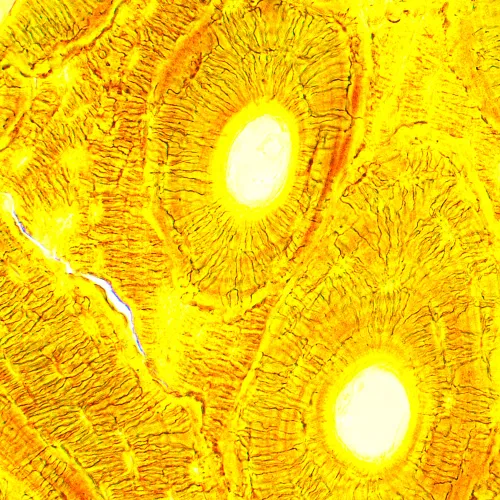

A MAGUS Bio 250T biológiai mikroszkóp egy professzionális műszer biológiai minták áteső fényben történő megfigyeléséhez. Az elsődleges megfigyelési technika a világos látóterű technika (használatra kész). A sötét látóterű, polarizációs és fáziskontrasztos technikák is rendelkezésre állnak, de ezekhez a mikroszkópot további tartozékokkal kell felszerelni. A mikroszkóp kiválóan alkalmas laboratóriumi és kutatási megfigyelésekre az orvostudomány, a gyógyszerészet, a kriminalisztika, a mezőgazdaság és más területek számára.

A végtelen síkú akromatikus objektívek tiszta, kontrasztos és részletgazdag képet biztosítanak, minimális torzítással. A tartozék objektívekkel és szemlencsékkel elérhető nagyítás 40-szeres és 1000-szeres közötti, de a felső határ további szemlencsékkel kitolható. Az optika végtelenre korrigált, ami azt jelenti, hogy további tartozékok illeszthetők az optikai útvonalba.